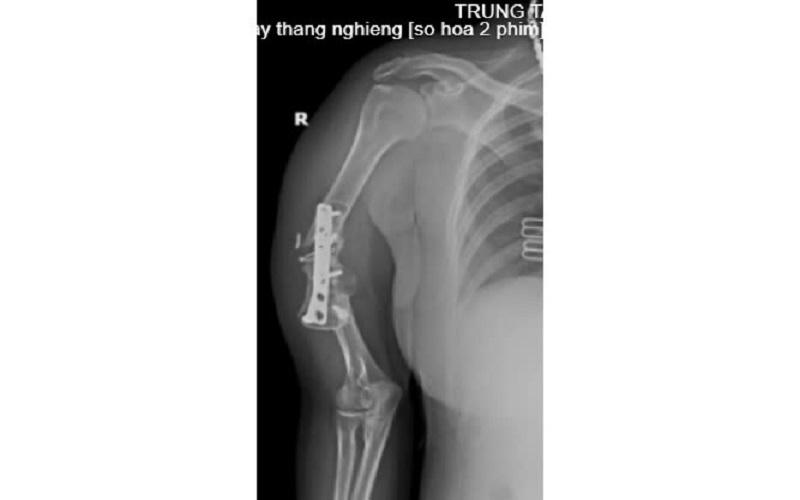

Cách đây 7 năm, sau một tai nạn, chị N.T.L bị gãy xương cánh tay phải, được phẫu thuật kết hợp xương bằng nẹp vít và mang theo phương tiện kết hợp xương kể từ ngày đó.

Năm 2023, chị N.T.L tiếp tục bị chấn thương vùng cánh tay phải nhưng không đi khám lại. Trong quá trình lao động và sinh hoạt hàng ngày, cánh tay phải của chị N.T.L dần bị biến dạng, gần đây vận động hạn chế và có cử động bất thường nên chị đã đến Trung tâm Y tế huyện Cẩm Khê để khám.

Tình trạng bệnh nhân trước khi mổ. |

Sau khi thực hiện các cận lâm sàng, Bác sĩ kết luận: Khớp giả xương cánh tay phải/Còn phương tiện kết hợp xương, chỉ định phẫu thuật ghép xương điều trị khớp giả.